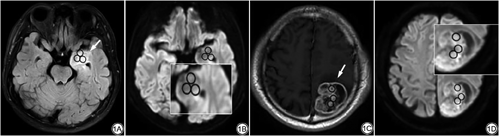

采用GE Signa Architect 3.0 T MRI系统对sDWI数据进行测量和分析。由2名分别在神经影像诊断方面具有3年及5年诊断经验的住院医师及主治医师分析图像,且对患者病理结果、临床资料和其他影像学检查结果不知情。分析步骤:(1)选择MUSE-DWI序列,进入主机系统sDWI界面,由已扫描的MUSE-DWI序列(b值为0和1000 s/mm2)通过后续计算合成b值范围为0~2500 s/mm2的DWI图像即sDWI;(2)结合T2 FLAIR及增强T1WI(T1WI+C)图像避开病灶出血、坏死、囊变区,选取相对容易识别的DWI高信号区域画取ROI测量病灶的信号强度(ROI范围为0.3~0.5 cm2);(3)根据以上原则选择特定b值三处不同ROI测量病灶的信号强度(图1),取其平均值。2周后2名观察者再次用同样的方法对这些数据进行重复测量。

sDWI不同b值高低级别胶质瘤信号强度比较显示:b值分别为500、800、1000、1200、1500、1800、2000、2200、2500 s/mm2时对应的信号强度在高低级别胶质瘤组间差异均具有统计学意义(P<0.001)(表1)。二元Logisitic回归分析显示b=2500 s/mm2的DWI图像对应的信号强度是预测高低级别胶质瘤的独立变量。ROC曲线分析显示b值为2500 s/mm2时诊断准确率最高,AUC为0.935,相应的敏感度为98%、特异度为87%。其余b值为2200、2000、1800、1500、1200、1000、800、500 s/mm2时AUC分别为0.929、0.925、0.919、0.915、0.909、0.905、0.859、0.757(表2)。sDWI图像随着b值升高,病灶与周围组织对比度越高,清晰显示瘤体周围囊变、坏死(图2)。